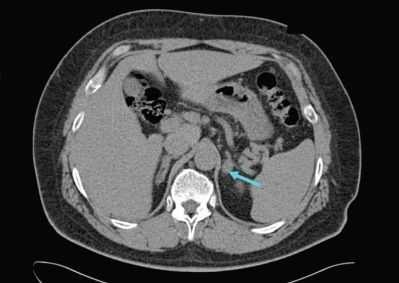

После подтверждения диагноза проводится компьютерная томография (КТ) органов брюшной полости для определения подтипа патологии. КТ проводится для определения причины гиперальдостеронизма - аденомы надпочечников, гиперплазии или карциномы (подозревается при обнаружении односторонней опухоли >4 см). Магнитно-резонансная томография (МРТ) не имеет преимуществ перед КТ, поэтому не рекомендуется в качестве стандартного метода обследования. Чувствительность КТ - 78%, специфичность - 75%.

Данные КТ надпочечников определяют дальнейшую тактику обследования и лечения. Например, если при КТ обнаружен односторонний гиподенсный узел (участок, отличающийся по плотности или цвету и четкими границами на изображении) и пациенту более 35 лет, следующий диагностический этап - исследование венозной крови надпочечников. Для уточнения того, где происходит перепроизводство альдостерона, проводят катетеризацию надпочечниковых вен и тест на венозную кровь надпочечников. Это золотой стандарт оценки латерализации первичного гиперальдостеронизма, с чувствительностью - 95% и специфичностью - 100%.